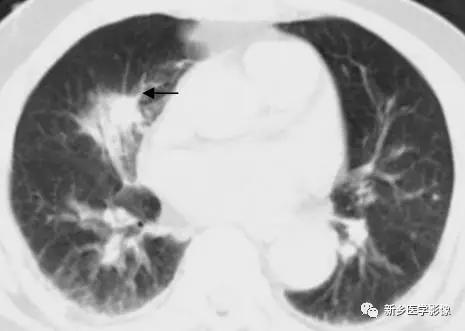

胸部CT肺窗圖;顯示毛刺徵(↑示)